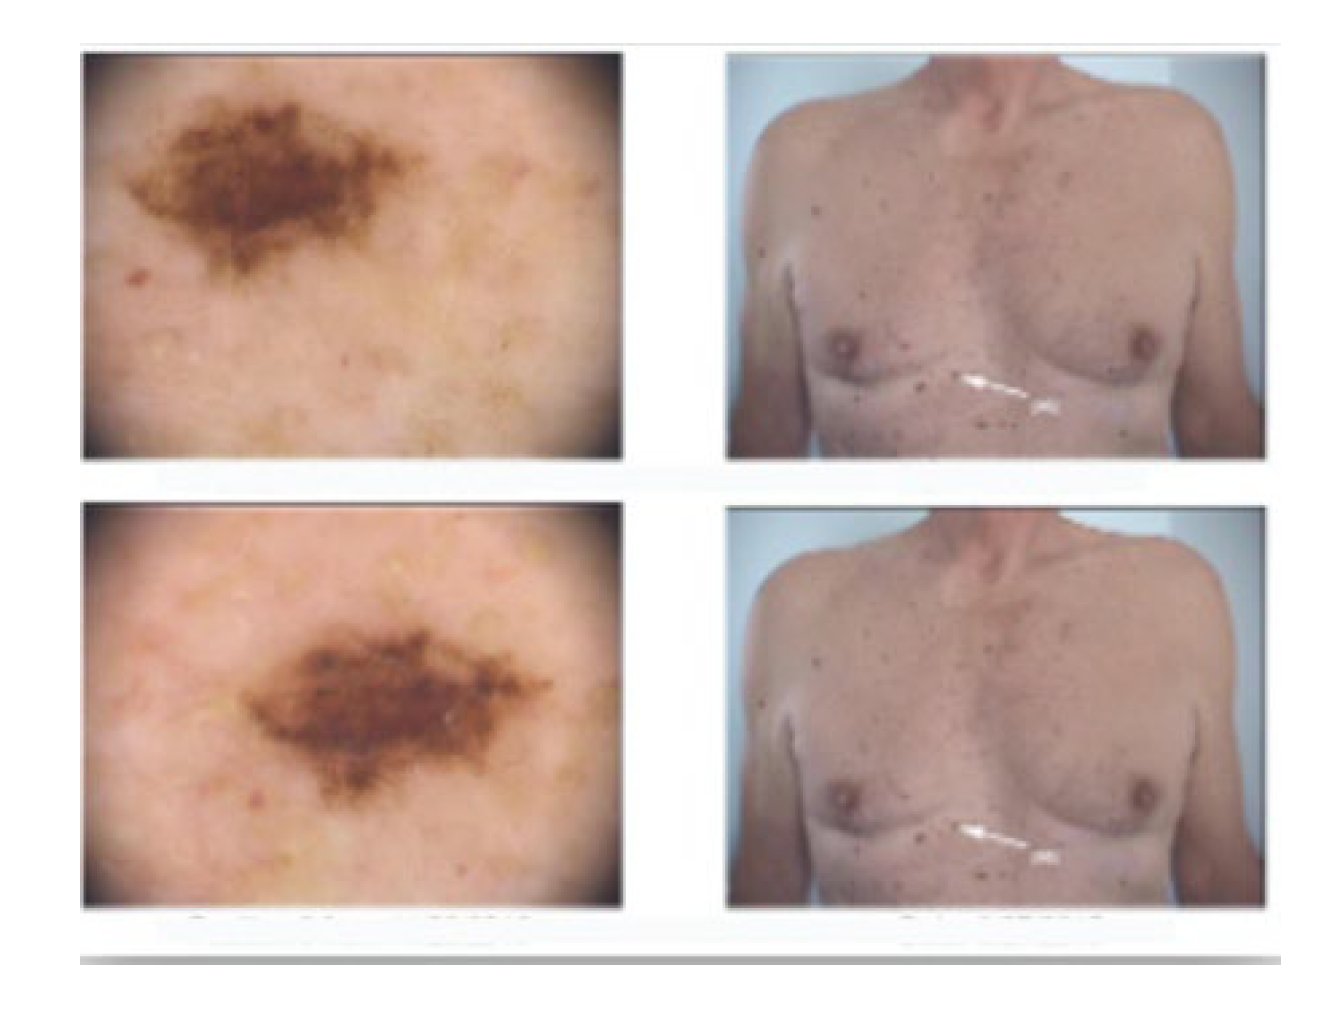

2. Case Presentation

3. Results